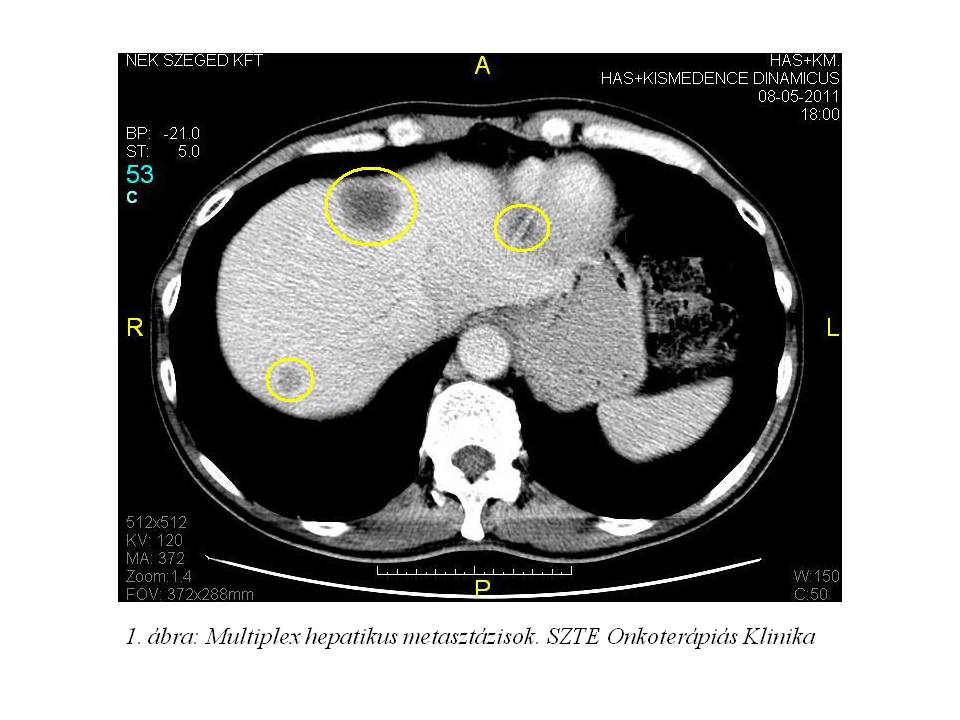

Az akkori staging has-, kismedence CT vizsgálata szerint a primer tumor a bal uretert szűkítette, a májban 4 áttétet írtak le. Mellkas röntgenjén multiplex tüdő áttétek, illetve lymphangitis carcinomatosa lehetősége merült fel. (1. ábra, 2. ábra)

2011.05.10-én a lokálisan előrehaladott, így irrezekábilis folyamat, valamint az áttétes betegség jelenléte miatt a passzázs biztosítása céljából palliatív megoldásként kétcsövű anus praeternaturalis készült az SZTE Sebészeti Klinikán. Az operáció során az áthajlás felett elhelyezkedő recto-sigmoideális tumort észleltek, mely a mesorectumot is beszűrte, a mesorectumban, a mesosigmában lévő nyirokcsomókban tumoros áttéteket tapintottak, melyek paraaorticusan is folytatódtak. A máj mindkét lebenyében diónyi metastasisokat észleltek.

Palliatív onkológiai kezelésként FOLFIRI-bevacizumab immunochemotherápia indult 2011.07.05-től. Az első re-stagingkor (3. ábra, 4. ábra) már parciális remissziót észleltünk (46% csökkenés) mind a primer tumor, mind a tüdő-, mind a máj metasztázisok méretében. 2011.10.18-ára (5. ábra, 6. ábra) a regresszió tovább nőtt (59%). A kezelés mellékhatásaként, az irinotecan infúziót követően jelentkező orrváladékozást (irinotecan okozta specifikus parasympatikus tünet) a további kezelések során sc. atropinnal premedikáltuk, míg Gr.I. postinfúziós vénagyulladását lokálisan kezeltük. A 30. ciklustól a kezeléseket követően émelygés jelentkezett, mely otthon szedett ondansetron hatására megszűnt. Az 53. ciklust követően Gr.III-as hasmenés, exsiccatio és Gr.IV. neutropénia miatt hospitalizálás vált szükségessé. Empirikusan indított intravénás, széles spektrumú, kombinált antibiotikum, sc. filgrastim kezelés, parenterális folyadék-, és elektrolit pótlás hatására állapota rendeződött. Kezelését ezt követően folytattuk, de az észlelt súlyos mellékhatások miatt 25%-os redukciót alkalmaztunk a kemoterápiás szerek dózisában.